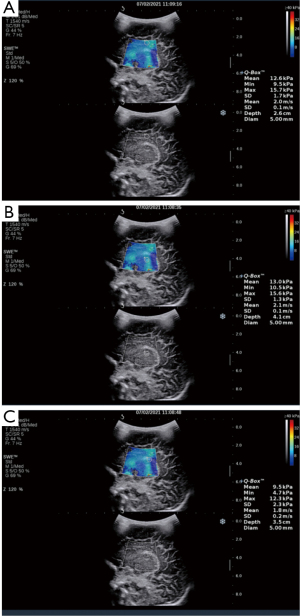

- The Emean measurements of the SWE sonogram for the regions of interest in the neonatal cranial lateral ventricular parietal cerebral white matter, thalamus, and choroid are shown in Figure 1.

Switching to the SWE mode, the Emeans of the affected neonate’s left/right paraventricular white matter, thalamus, and choroid were measured via a sagittal sweep of the fontanelle, and the Emeans were averaged over 3 measurements. Young’s modulus value (E=3ρc2, where E represents the tissue elastic modulus, ρ represents the tissue density, and c represents the shear wave propagation velocity) were automatically calculated by the machine (8). All procedures were performed by the same physician. A coupling agent was applied thickly during the examination; only minimal pressure was placed on the affected fontanelle. The area of interest for the Emean measurement in the paraventricular cerebral white matter was placed in the area of the cerebral white matter at the peripheral edge of the corpus callosum. The area of interest for the Emean measurement in the thalamus was placed in the middle of the thalamus. The area of interest for the Emean measurement in the choroid was placed at the head of the choroid near the caudate sulcus of the thalamus. A 3 cm × 4 cm sampling frame size was chosen to display the 3 regions of interest simultaneously and reduce the sampling time.